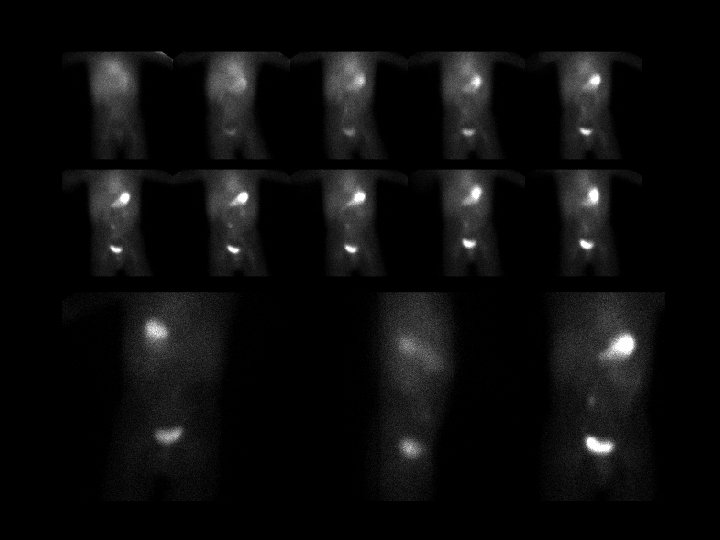

Renal Duplication • • 1. 1 m. Ci Tc-99 m MAG 3, i. v. delayed uptake and no excretion in the right upper pole and filling defect in the bladder dilated upper pole and ectopic ureterocele by US Weigert-Meyer Rule – upper pole obstructs, ureter inserts medially and caudally – lower pole refluxes, inserts normally